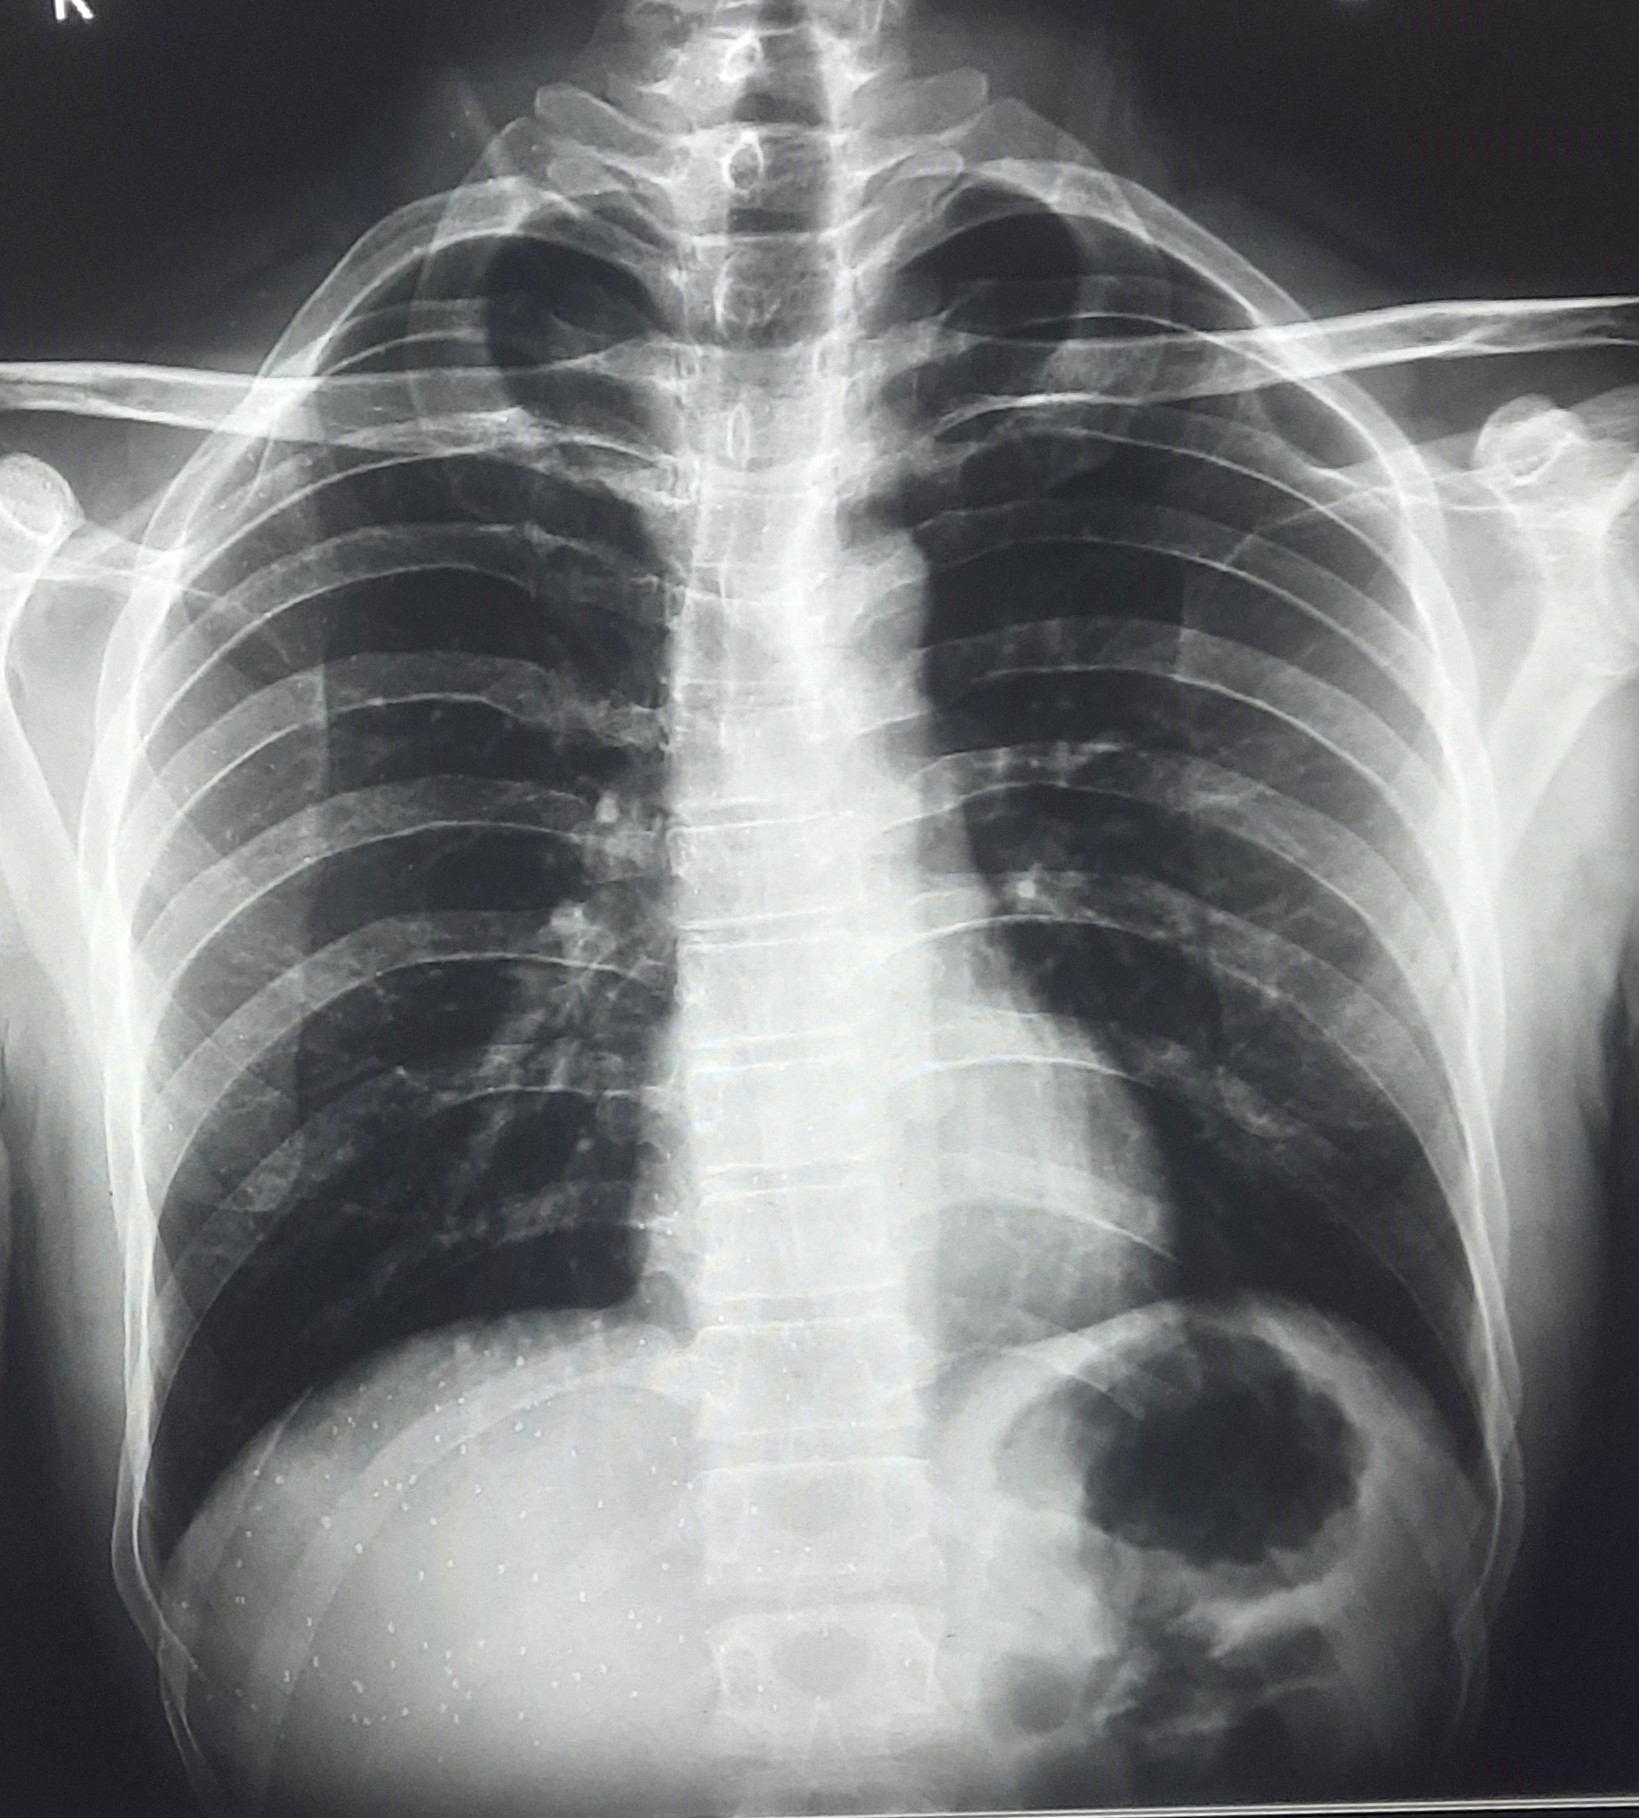

| 341 | IGGMC, Nagpur, Nagpur | P2 | 29-4131 | Tarzan Sahu | Consent taken on Paper | 34 Yrs. |

Provisional Diag : Bilateral Consolidations

Final Diag : Liver Disease |

Non-TB Case (Confirmed) | Faty Liver With Left Middle Zone, Lower Zone Consolidation With Symptomatic Effusion | Abnormality visible on x-ray |